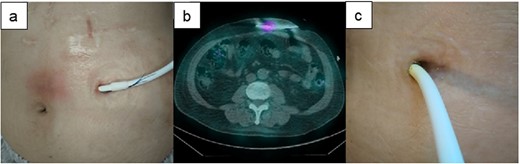

A 60-y-old man with ischemic cardiomyopathy underwent LVAD implantation (HeartMate II™, Abbott Co., Abbott Park, IL, USA) 2 y before being admitted to our hospital because of pain and skin redness above the umbilicus. He had no skin induration and tenderness at the DLES; however, redness, local increase in temperature, and skin induration and tenderness were noted above the umbilicus (Fig. 3a). As the inflammatory area was far from the DLES, surgical debridement and associated relocation of the exit site were considered. 67Ga SPECT showed a high signal up to 5 cm inside the DLES (Fig. 3b). The empirical antibiotics were administered intravenously after collection of cultures of exit site and drained fluid. First, the catheter cleaning method via the DLES was executed, daily bedside debridement with 10% silver nitrate solution was performed via the DLES to eliminate the contaminated tissue for about 1 week. In this patient, the DLES and spot with redness were distant, and it was suspected that the infected granulation tissue affected the discharge of the exuded solution. Therefore, monofilament nylon threads were inserted for continuous drainage (Fig. 3a). Simultaneously, daily irrigation using an intravenous indwelling catheter was continued with a 1000-ml saline solution for about 1.5 months (Fig. 2e). Although repeated culture of drained fluid did not detect the definitive pathogenic bacterium, intravenous antibiotics were used for about 6 weeks but were then switched to oral antibiotics. The spot with redness healed, and the patient was discharged from the hospital 2 months after admission (Fig. 3c). This patient was readmitted for a similar DLI 4 months later and was treated with the same catheter method for about 3 weeks. Then, DLI did not reoccur until 1.5 y later.

The clinical course of development of the DLI in Case 1. (a) There was some distance between the DLES and the spot with redness and induration. (b) 67Ga SPECT shows high signalization within reach of the cotton swab and intravenous catheter from DLES. (c) The spot with redness and induration healed after treatment with this catheter method.